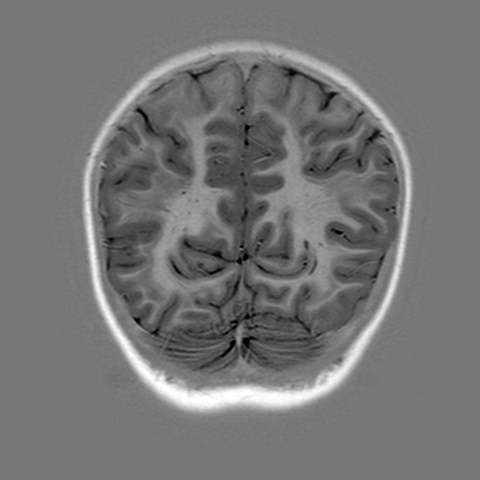

Band Heterotopia

Ask for: